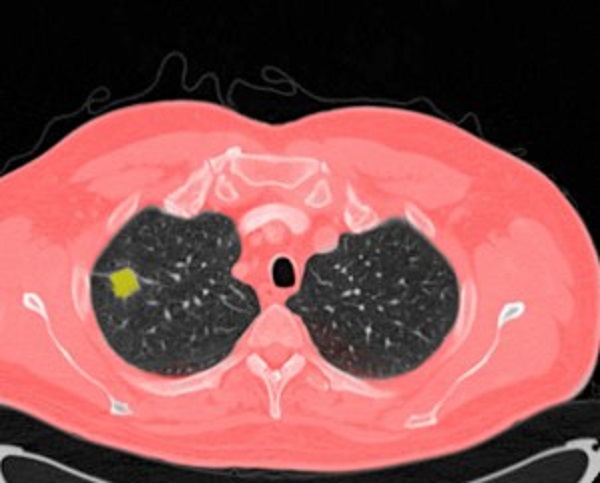

肺结节是肺部影像上直径不超 3 厘米的局灶性阴影,按密度分为实性、磨玻璃和部分实性结节。实性结节多由肺部良恶性病变形成;磨玻璃结节可能是炎症、肿瘤早期表现;部分实性结节恶性概率较高需重点关注。肺结节成因复杂,除恶性肿瘤外,病原体感染后留下的瘢痕、长期粉尘烟雾暴露,以及肺部良性肿瘤、自身免疫性疾病都可能引发。

低剂量螺旋 CT 是检测肺结节的有效手段,建议 50岁以上、吸烟或被动吸烟、慢阻肺、长期粉尘烟雾石棉暴露、有肺癌家族史等高危人群每年筛查。判断肺结节良恶性需综合评估:良性结节边缘光滑,恶性多有毛刺,成分叶状;结节越大恶性概率越高;动态观察变化也很关键,病理检查是诊断“金标准”。